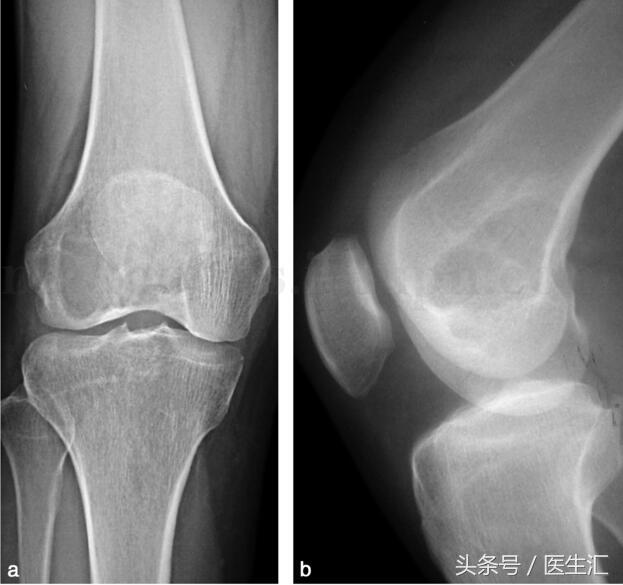

影像學檢查:X 線示右股骨遠端骨端發(fā)生的一個偏心、基質(zhì)均勻、皮質(zhì)膨脹、皮質(zhì)無骨破壞、無骨膜反應(yīng)、無軟組織腫塊的溶骨性破壞(圖29‐1a,圖29‐1b)。CT 示右股骨遠端骨端的溶骨性破壞,基質(zhì)均勻,注射造影劑后,病變強化,CT 值由強化前的40HU 增加到強化后的110HU(圖29‐2a~圖29‐2c)。

圖29‐1

a﹒右股骨下段外髁部溶骨性骨破壞(X 線正位片);b﹒右股骨下段外髁部溶骨性骨破壞(X 線側(cè)位片)